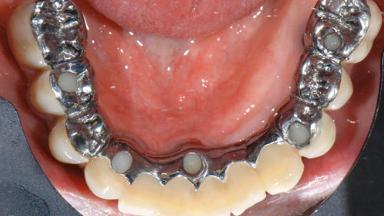

A 77-year-old male patient was referred for the management of frequent and repeated acrylic fracture of his existing mandibular fixed full-arch implant-supported metal/acrylic prosthesis. He also complained about softtissue soreness and the lack of retention and stability of his maxillary removable partial metal/acrylic prosthesis. Both prostheses had been delivered two years previously as part of his full-mouth rehabilitation (caries, tooth wear, tooth fracture). His medical history revealed high blood pressure, controlled with the use of antihypertensive medication.

Prosthesis Type FDP

Retention Screw-retained, with 4 or more splinted implants Screw-retained, with 4 or more splinted implants